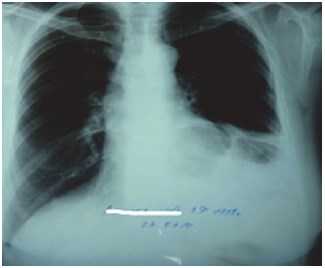

На этапе предоперационного обследования выполнялся тщательный сбор анамнеза и жалоб. Только у 6 пациентов были жалобы на изжогу, отрыжку кислым в течение нескольких лет до поступления в стационар. У больного с ущемленной параэзофагеальной грыжей и ранее имели место периодические приступы боли в грудной клетке. Жалобы на дисфагию, кашель, осиплость голоса не наблюдались ни у одного больного. Пациенты, попавшие в отделение экстренно, имели схожие симптомы при поступлении: многократную обильную рвоту, умеренные боли в животе. У двух пациентов параэзофагеальная грыжа была выявлена случайно во время планового обследования и не сопровождалась симптомами. Из инструментальных методов обследования перед оперативным лечением всем больным выполнена обзорная рентгенограмма органов брюшной полости и грудной клетки, рентгенконтрастное исследование пищеводно-желудочного перехода, водно-перфузионная манометрия пищевода с измерением давления нижнего пищеводного сфинктера, фиброгастроскопия, магнитно-резонансная томография диафрагмы (рис. 1, 2).

Рис. 1. Обзорная рентгенограмма органов грудной клетки: неоднородное затемнение левого легочного поля с участками просветления с четкими контурами - петля поперечной ободочной кишки в полости заднего средостения